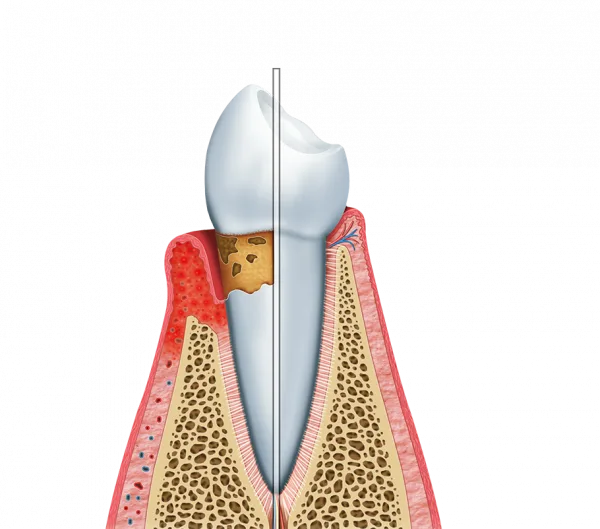

A limpeza profunda gengiva é um procedimento essencial para a saúde bucal.

Ela vai além da limpeza convencional, abordando problemas que podem afetar a gengiva e os dentes.

Ela remove a placa bacteriana e o tártaro acumulados, que são responsáveis por inflamações.

Um dos principais objetivos da limpeza profunda gengiva é a prevenção de doenças periodontais.

Essas condições podem levar à perda de dentes se não forem tratadas adequadamente.

Com a limpeza, é possível evitar a gengivite e a periodontite, que são as doenças mais comuns.

O processo de limpeza profunda gengiva envolve várias etapas.

Primeiro, o dentista realiza uma avaliação detalhada da saúde bucal.

Em seguida, a remoção do tártaro e da placa bacteriana é feita com o uso de ultrassom e instrumentos manuais.

Por fim, a gengiva é tratada para promover a cicatrização.